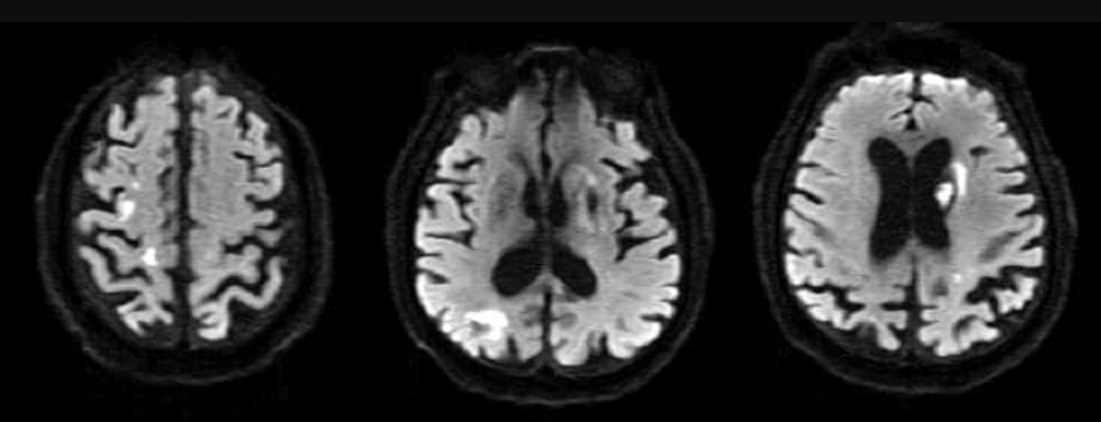

Hình 4 - Hình ảnh đột quỵ thiếu máu não đa ổ ở bệnh nhân sau nhồi máu cơ tim